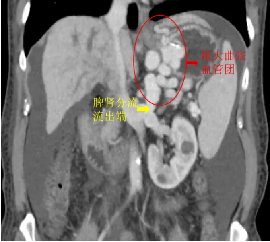

雪上加霜的是,患者门静脉CT血管造影术(CTA检查)示其除了胃静脉曲张还伴随着粗大的脾肾分流,这意味着针对胃静脉曲张出血普遍采取的手段——组织胶注射栓塞治疗,出现异位栓塞的风险将会显著增高,组织胶通过粗大的脾肾分流进入体循环,极易造成重要器官栓塞等严重并发症。

为实现胃底巨大曲张静脉的封堵,减少再发出血和异位栓塞的风险,消化内科与肝胆介入科共同研讨患者病情后,决定选择行改良球囊阻断分流道联合内镜下胃静脉曲张栓塞术,用球囊进行封堵,避免了严重并发症的发生。

在介入中心导管室,肝胆介入科主任张跃伟带领廖勇、刘影医师,经右股静脉插管至脾肾分流道流出端,交换球囊随后顺利进入分流道,充盈的球囊成功阻断分流道,这一极易引发器官栓塞的“雷”被排掉了!

随后,消化科副主任任渝棠和陈涛医师在胃镜下穿刺胃底巨大曲张静脉,胃的蠕动、呼吸道起伏影响食管而导致的蠕动,双重加大操作的难度。在医生们默契的配合下,混有造影剂示踪的组织胶被打入了胃壁外曲张静脉,得益于球囊的阻断,组织胶未经过脾肾分流血管便进入了体循环,最终实现了胃底巨大曲张静脉的封堵。